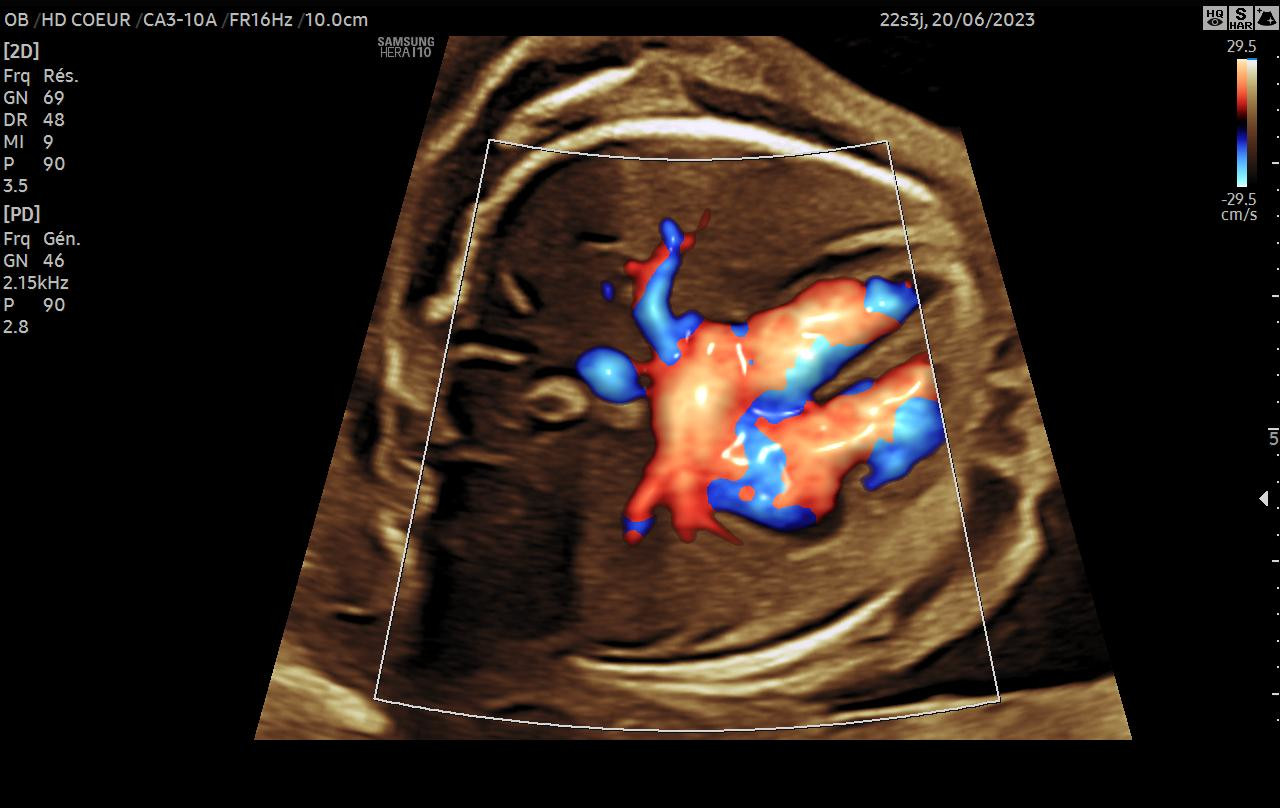

Échographie de datation, du 1er trimestre, morphologique, 3D ou 4D, gémellaire, etc.